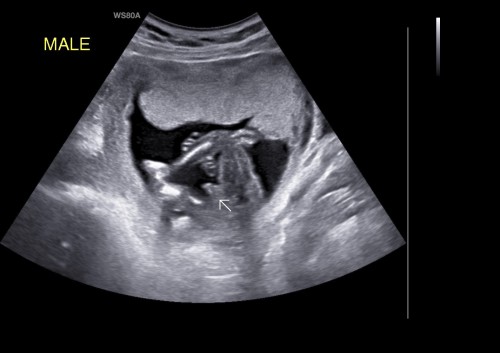

กำหนด12/04/66 อยากรู้ว่าได้ลูกชายหรือลูกสาวค่ะ บ้านนี้ทีม ลูกชาย 🥵ลูกชาย4คนไปเลย ลุยๆๆๆๆ😅

ผลนิฟลูกชายค่ะ คลอด21เมษา รอหมอซาวด์ให้19นี้ลุ้นว่าจู๋จะโผล่รีป่าวค่ะ รอบก่อน12สัปดาห์น้องนอนคว่ำค่ะ

บ้านนี้ หมอบอกเห็นจู๋ ค่ะ แต่ไม่คอนเฟิร์ม ต้องรอ5เดือนคร้า 7/4/66จ้า